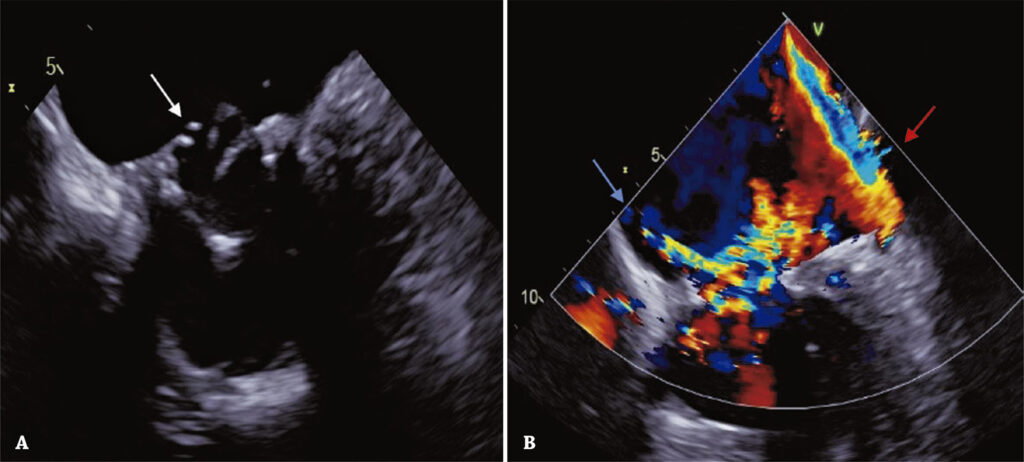

Transcatheter mitral valve-in-valve replacement has recently emerged as an increasingly common alternative for high surgical risk patients. We report a case of a successful transseptal transcatheter mitral valve-in-valve replacement for the treatment of a bioprosthetic mitral valve degeneration and severe regurgitation, in an 86-year-old patient who had undergone transcatheter aortic valve-in-valve procedure 6 years ago. This case emphasizes the crucial role of a careful preoperative assessment using multimodality imaging to plan the procedure, in a patient with higher risk of left ventricular outflow obstruction due to the previous transcatheter aortic valve-in-valve procedure.